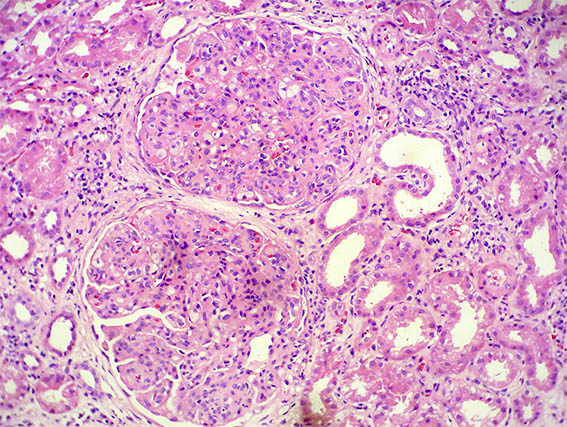

A renal biopsy was done, see the images.

Figure 1. H&E, X100.